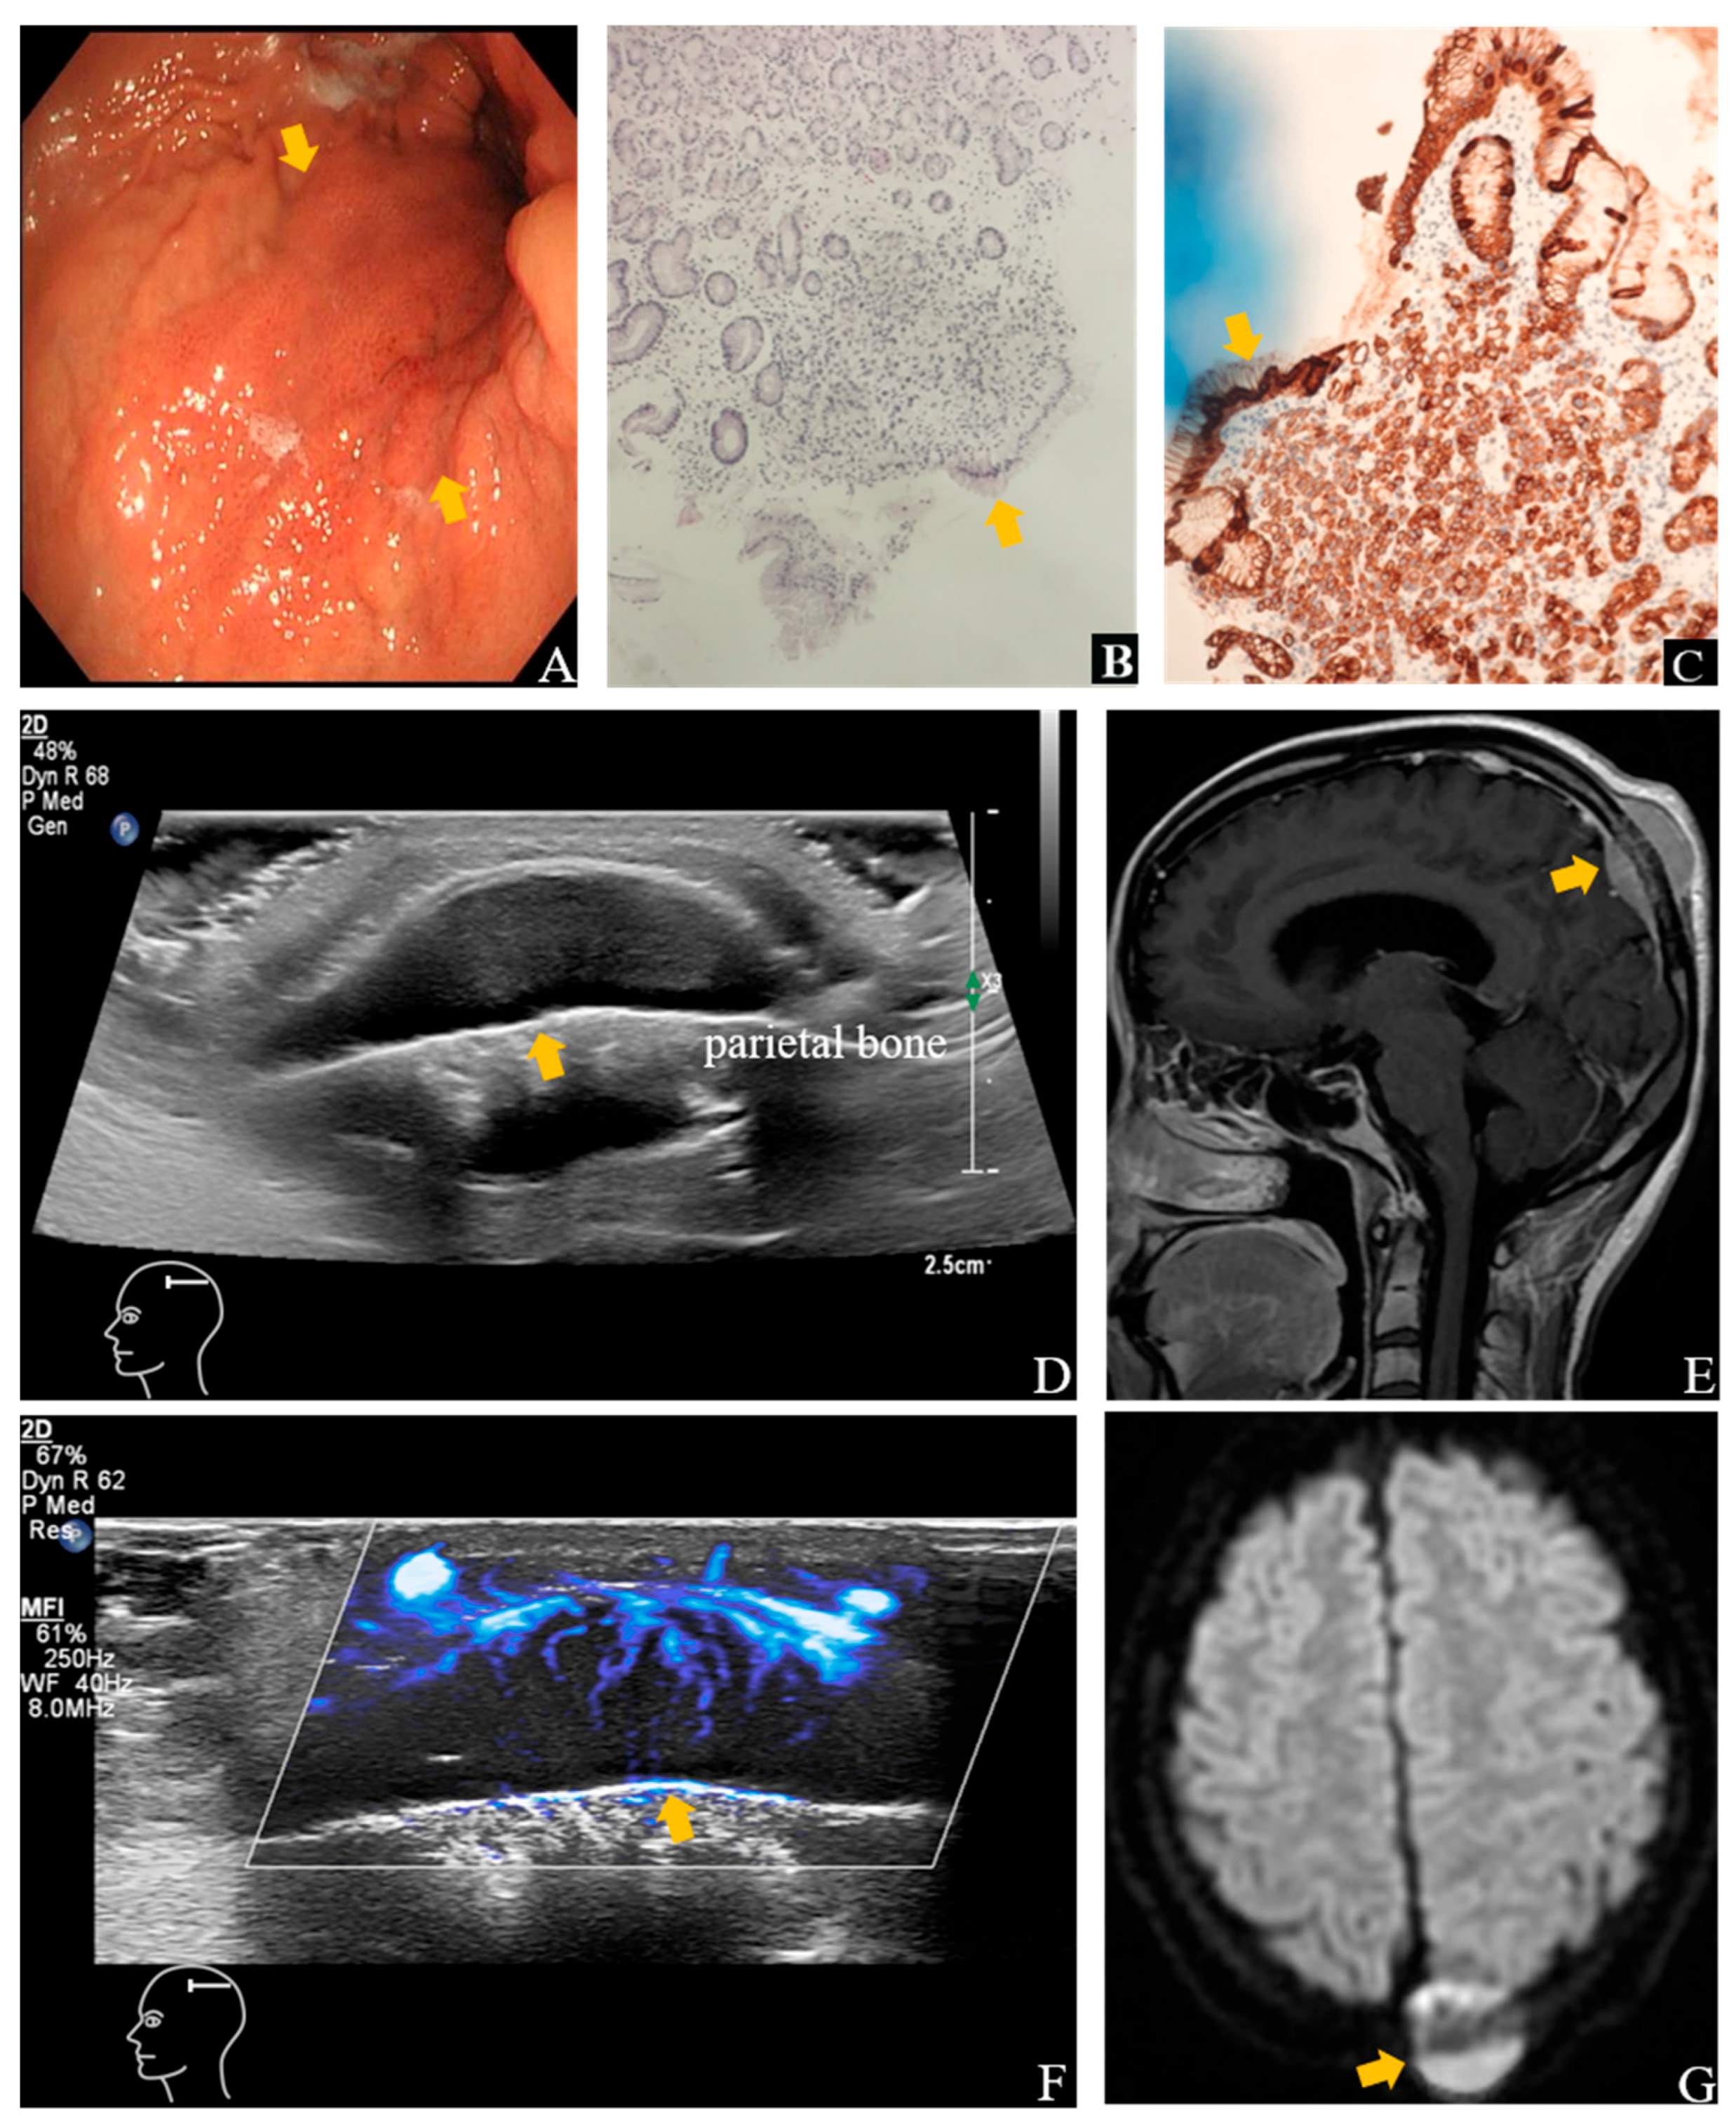

Figure 1. Ultrasound (US) and contrast-enhanced MRI images show the lesion in the left parietal bone. An endoscopic biopsy ((A), arrow) performed four months earlier in a 26-year-old woman with epigastric discomfort confirmed SRCC on histopathological examination ((B), arrow), Hematoxylin and Eosin staining (H&E), ×10 and (C), arrow), Immunohistochemical Staining (IHC), AE1/AE3 (+)). She complained of right intercostal pain and palpable, firm, immobile masses over the scalp, left neck, and lower abdomen. Her maternal grandmother had a history of cardia cancer. Gray-scale image showed a 3.1 × 2.9 × 0.8 cm solid mass in the subgaleal layer over the left parietal region adjacent to the skull (arrow), with ill-defined margins and abundant vascularity (arrow) on SMI (D,F). Disruption of the adjacent calvarial cortex was noted. Contrast-enhanced MRI of the head revealed a hyperintense lesion in the left parietal bone (arrow) with osteolytic destruction (E,G), consistent with osseous metastasis. One month later, follow-up ultrasound showed enlargement of the scalp lesion to 3.7 × 3.6 × 1.5 cm, and after two months, further progression to 5.7 × 5.1 × 2.0 cm.